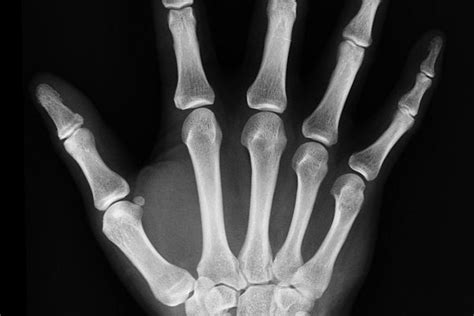

Vzhľadom na neistotu a potenciálne riziko spojené s prehltnutím akéhokoľvek cudzieho telesa, je návšteva lekára nevyhnutná. V tomto konkrétnom prípade bol naplánovaný termín u lekára a následne röntgenové vyšetrenie. Röntgenový snímok je štandardným diagnostickým nástrojom, ktorý lekárom umožňuje presne lokalizovať prehltnutý predmet v tráviacom trakte a posúdiť jeho charakter.

V prípade prehltnutia zlatého prsteňa, ktorý je hladký a bez ostrých hrán, je prognóza často priaznivá. Mnohé malé, hladké predmety prejdú tráviacim systémom bez akýchkoľvek komplikácií. Lekár na základe röntgenového nálezu rozhodne o ďalšom postupe.